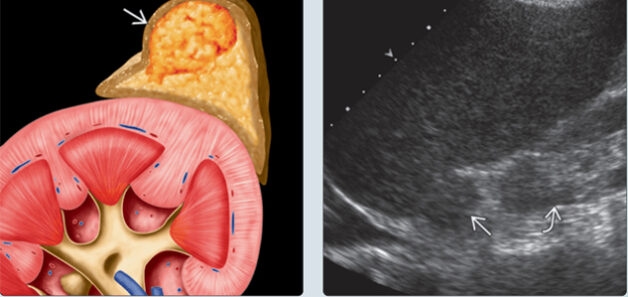

Tuyến thượng thận có cấu tạo gồm vỏ thượng thận và tủy thượng thận. Tùy thuộc vào nơi khối u phát triển và loại hormone khối u tạo ra mà người bệnh có thẻ có các triệu chứng khác nhau.

Hình ảnh mô tả khối u tuyến thượng thận trên giải phẫu và trên hình ảnh siêu âm.